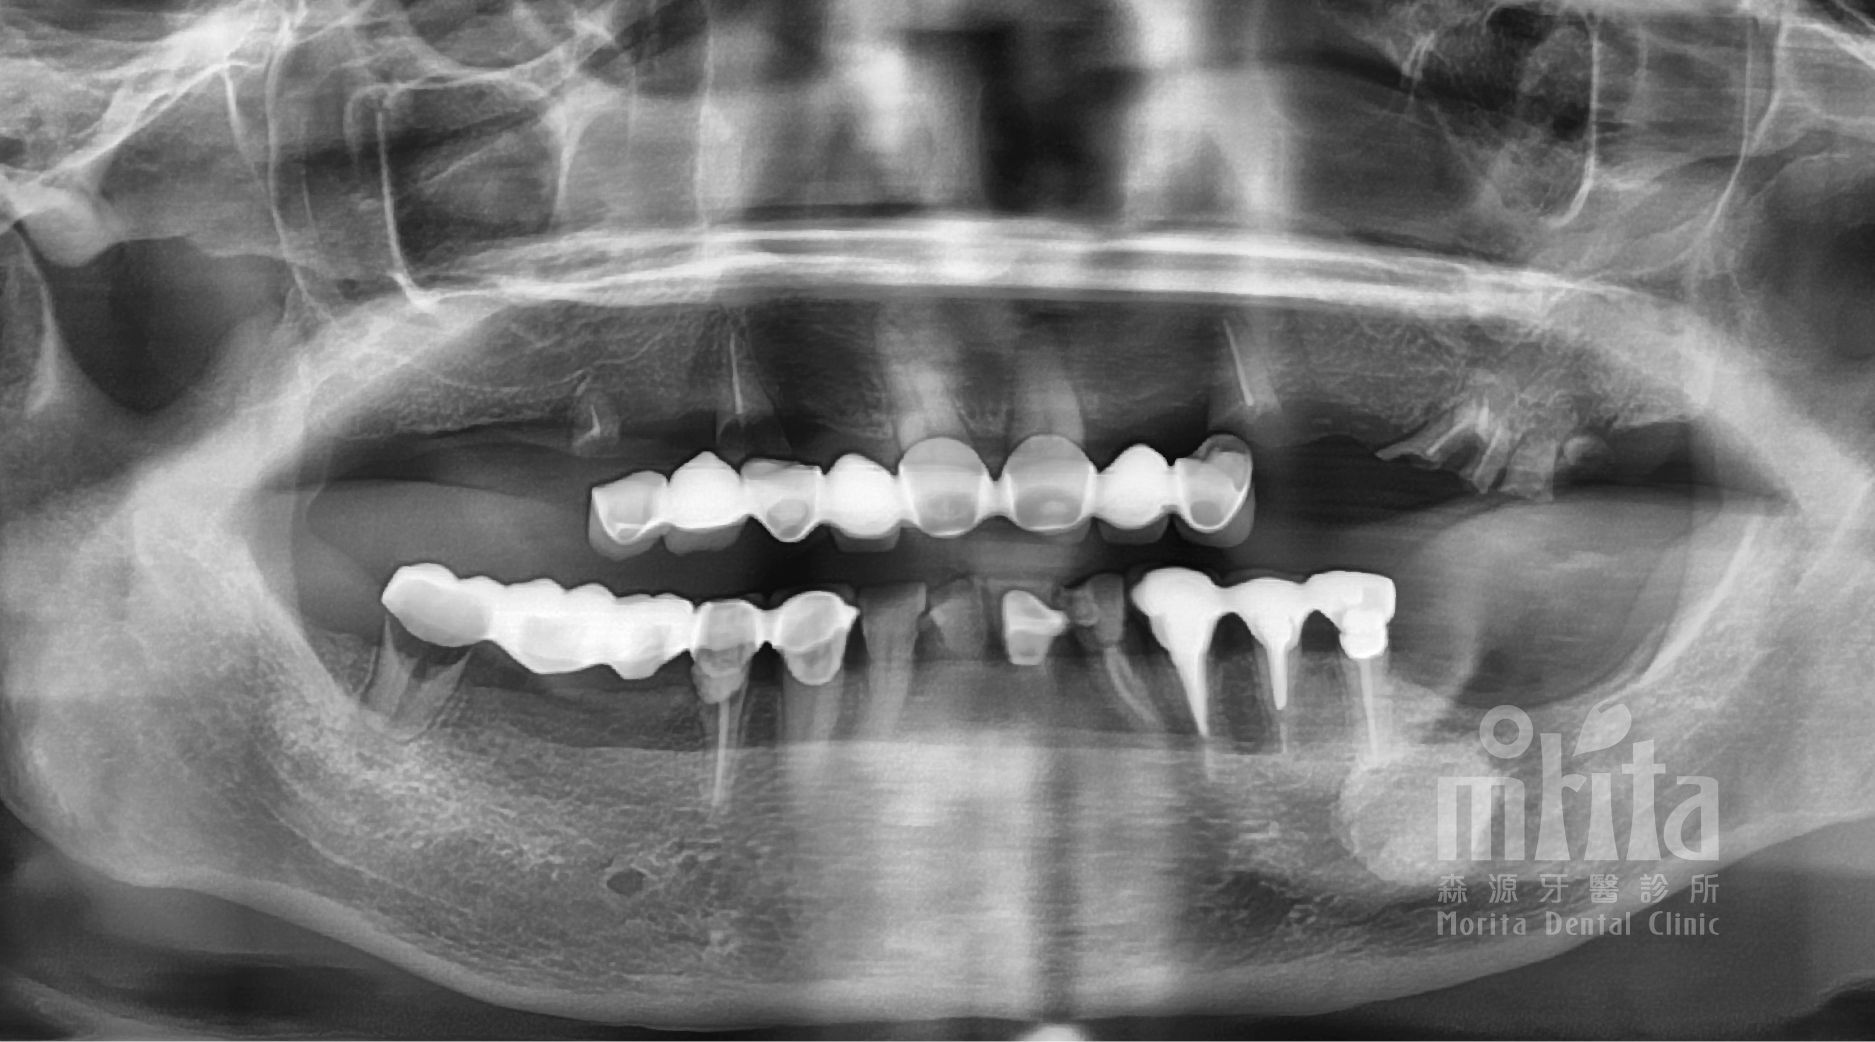

呂阿姨是為虔誠的佛教徒,吃全素的她因爲牙齒不好,導致吃蔬菜時都需要把青菜煮得很久很爛之後,才能方便進食,很是辛苦。